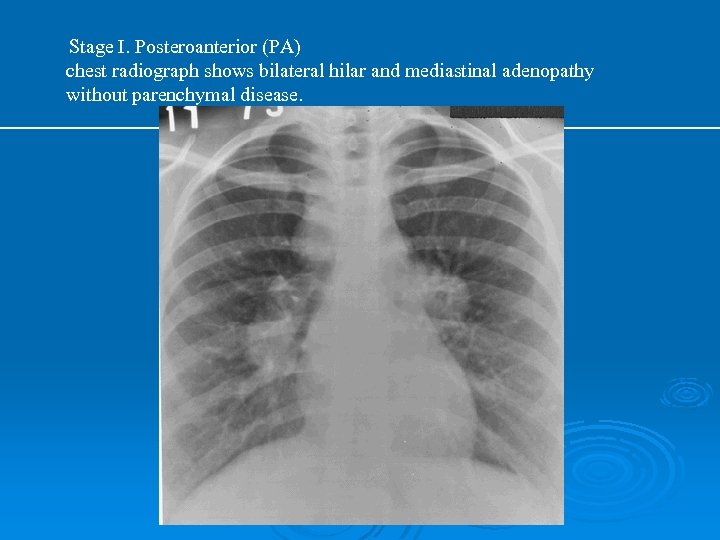

PA AKCİĞER GRAFİSİ Ø Grafiye göre evreleme yapılır: Evre 0: normal Ø Evre 1: bilateral hiler, mediastinal veya paratrakeal LAP Ø Evre 2: evre 1 + parankimal infiltrasyonlar Ø Evre 3: LAP ın eşlik etmediği diffuz pulmoner parankimal infiltrasyonlar Ø Evre 4: LAP ın eşlik etmediği fibro-kistik interstisyel akciğer hastalığı Ø

Stage I. Posteroanterior (PA) chest radiograph shows bilateral hilar and mediastinal adenopathy without parenchymal disease.